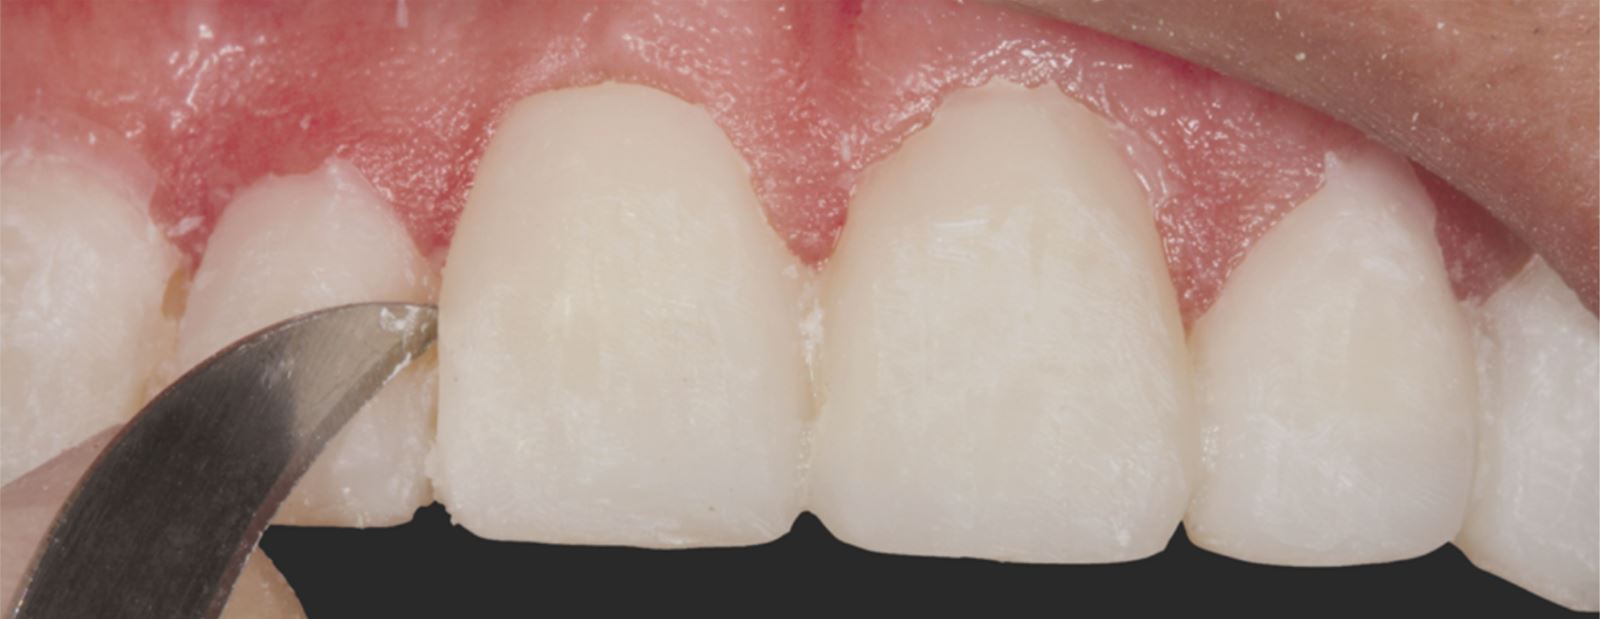

Příprava sulku:

Do gingiválního sulku byla vložena pletená retrakční vlákna Ultrapak™ velikosti #0 k přípravě pro leptání.

Modelace anatomie fazet

K modelaci anatomie fazet byly použita diamantová brouska ve tvaru míče na ragby a dlouhý tenký diamantový brousek. K vytvoření linií Retzia (SR lines) byla použita lobulární diamantový brousek (segmentovaný, „laločnatý“ tvar). Počáteční leštění proběhlo s Jiffy™ Natural, finální lesk byl dosažen přípravkem Ultradent™ Diamond Polish Mint a Jiffy™ Goat Hair Brush (není dostupný v Evropě), aby nedošlo k odstranění terciární anatomie.